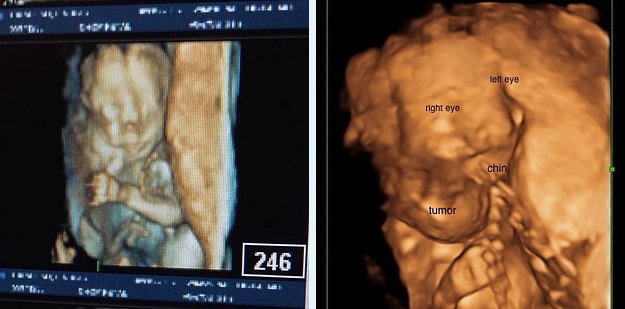

Cuando Lindsay estaba en la semana 18 de gestación, durante un estudio de rutina, los médicos descubrieron algo inusual. ¡En el cuello del bebé no nato crecía rápidamente la inflamación!

Al principio, los médicos se mostraban optimistas, y esperaban que la enfermedad se detuviera por sí sola, para ayudarlo después del nacimiento. ¡Sin embargo, dos semanas después, el tumor se duplicó!